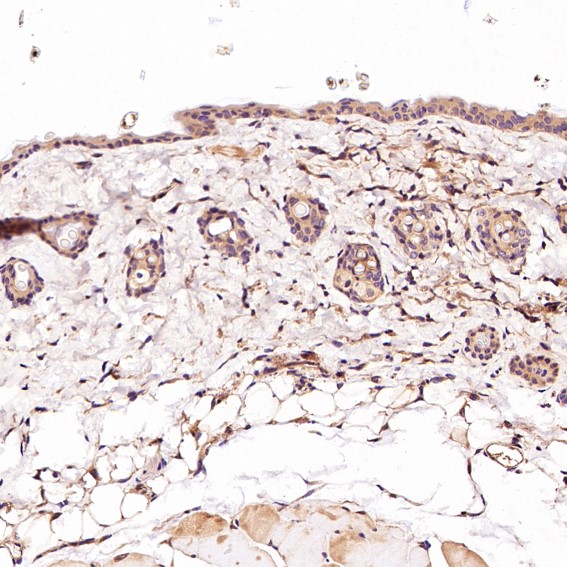

CD45 Antibody (CY5311)

Application:WB,IHC,ICC/IF,FC

Reactivity:Human

Source:Rabbit mAb